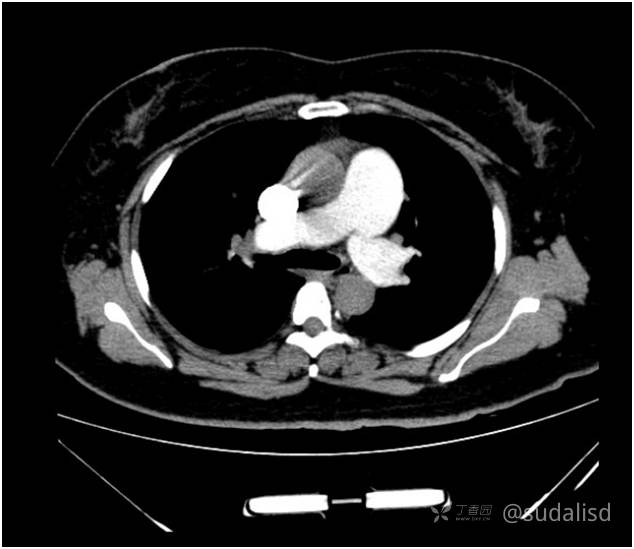

肺动脉CTA未见肺动脉主干有充盈缺损。见下面动态图和静态图。